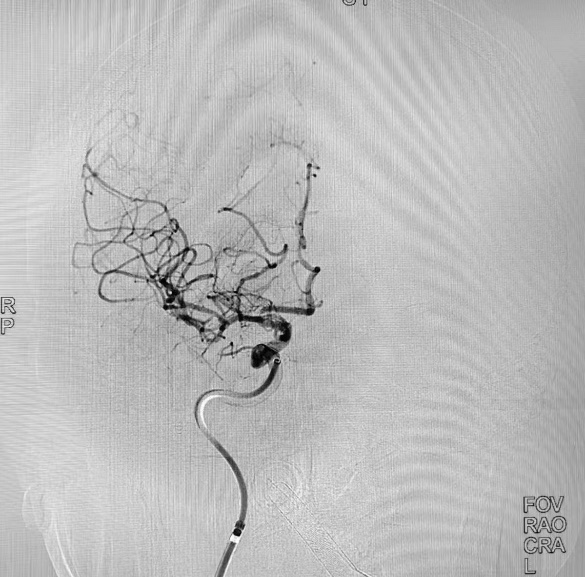

术前DSA

“时间就是大脑”,治疗每延误1分钟,将有190万个脑细胞死亡,等不来、缓不得、也拖不起,轻则导致偏瘫、失语,重则导致死亡。左大爷被送往手术室后,纪文军主任医师带领介入治疗团队立即对他进行了全脑血管造影术检查,术中进一步确诊患者的右侧颈内动脉末端完全闭塞,远端血管不显影。随后,由纪文军主任医师主刀,在李涛副主任医师和郭谢凡住院医师配合下,应用国内先进的抽吸+支架结合取栓,用快的速度使闭塞的右侧颈内动脉实现了再通,再次造影显示右侧颈内动脉血供恢复通畅,达到血流三级再通。手术过程非常顺利。